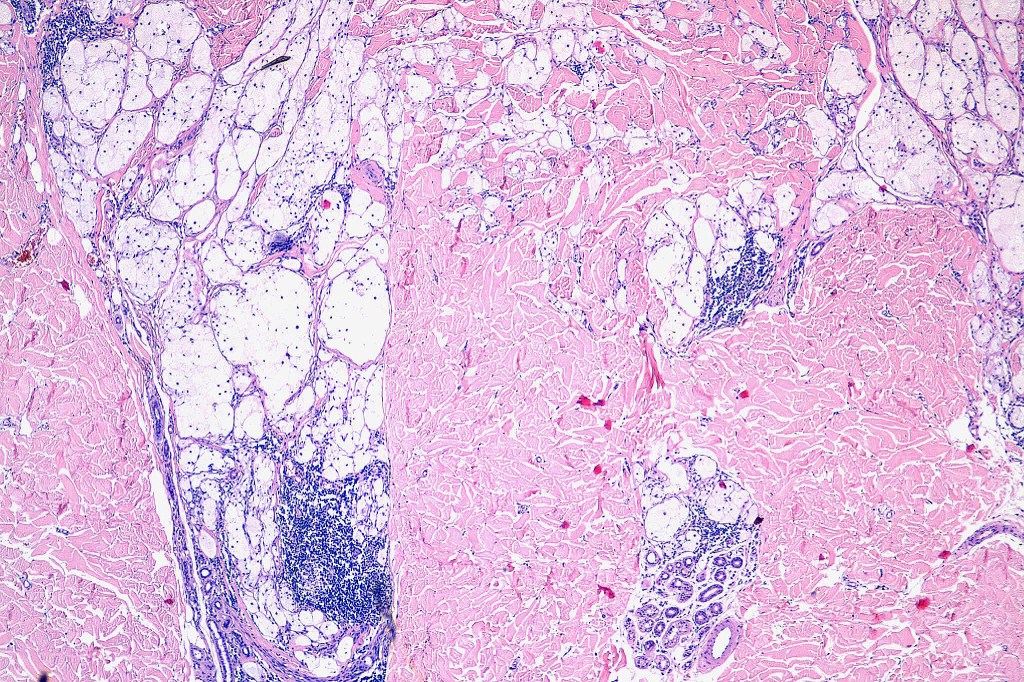

Histological features

•May affect the tumor in part or whole

•Enlarged cells with copious eosinophilic, foamy or clear cytoplasm (some authors include melanoma with clear cell change in the same category)

•Variable pigmentation

•Nuclei vesicular or hyperchromatic

•Pleomorphism is not generally marked and indeed can be very subtle

•Variable mitotic activity